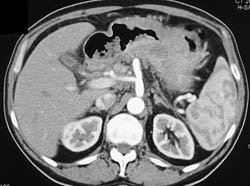

Gastric Outlet Obstruction With Gastric Cancer